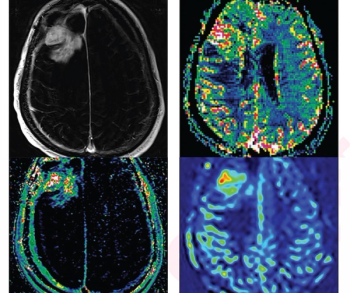

Based on surveys of neuro-oncologists taken before and after the use of MRI perfusion imaging and spectroscopy in patients with high-grade gliomas, researchers found the advanced imaging would have led to a greater than fivefold change in patient management in comparison to previous research.